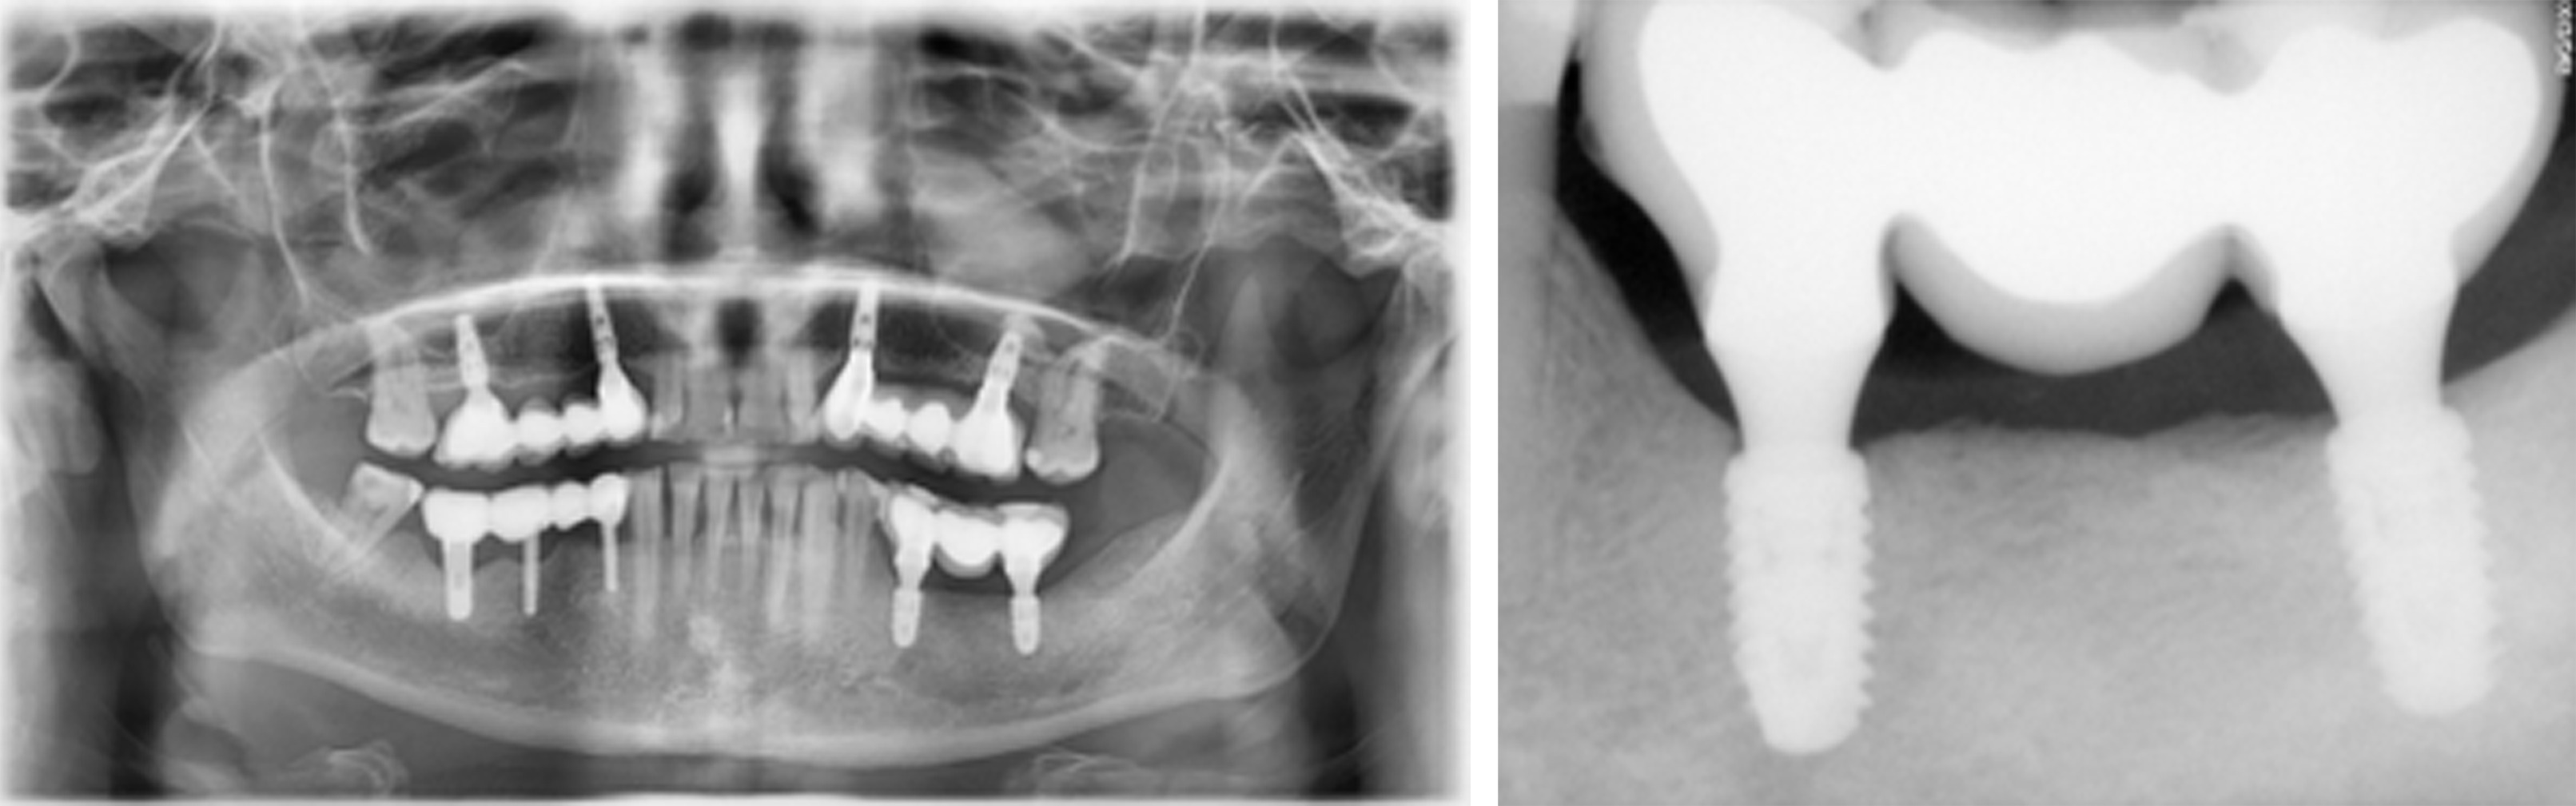

A female patient in her 40s presented with suppuration of increasing volume in Quadrant III and reported a 5-year pain-free progressive evolution. The patient was otherwise asymptomatic with no pertinent family or medical history. Clinical examination revealed association of the suppuration with a bridge on implants from Tooth 35 to 37 (Figure 1) and radiographic examination confirmed bone loss characteristic of moderate peri-implantitis (Figure 2). It was thus determined that the original implants would be removed, followed by GBR to facilitate proper three-dimensional placement of new implants.

Figure 2. Presenting panoramic radiograph confirmed advanced bone loss characteristic of moderate peri-implantitis